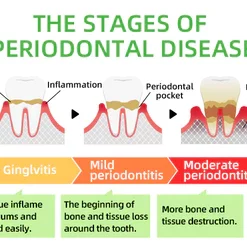

Every day, food residues in our mouths create a breeding ground for various bacteria and microorganisms within the oral cavity. This can result in a range of oral health issues, including bad breath, mouth ulcers, yellow teeth, cavities, calculus buildup, gum inflammation, bleeding gums, tooth sensitivity, weakened or missing teeth, swollen gums, toothaches, loose teeth, tooth loss, and even the risk of oral cancer.

As these conditions worsen, you may experience persistent bad breath, gum inflammation, and other problems. Bacteria continue to harm your gums, leading to issues like bleeding, pain, and redness. Without timely intervention, these oral problems can escalate, potentially causing periodontitis, dental plaque, dental calculus, loose teeth, tooth pain, and eventually tooth loss.

Dental caries develop when germs damage tooth enamel and gradually penetrate into the dentin and even the pulp. This can result in bad breath, toothaches, weakened teeth, and potential tooth loss. The presence of caries often triggers a chain reaction, causing healthy teeth to be affected as germs spread to adjacent teeth.

Remove Calculus

Calculus is calcified dental plaque that inflames the gums, which can lead to bone loss, loose teeth, tooth sensitivity, etc. FURZERO™ Herbal Brightening Oral Repair Foam can help eliminate dental plaque and remove stubborn calculus attached to teeth, making your teeth white and healthy again.